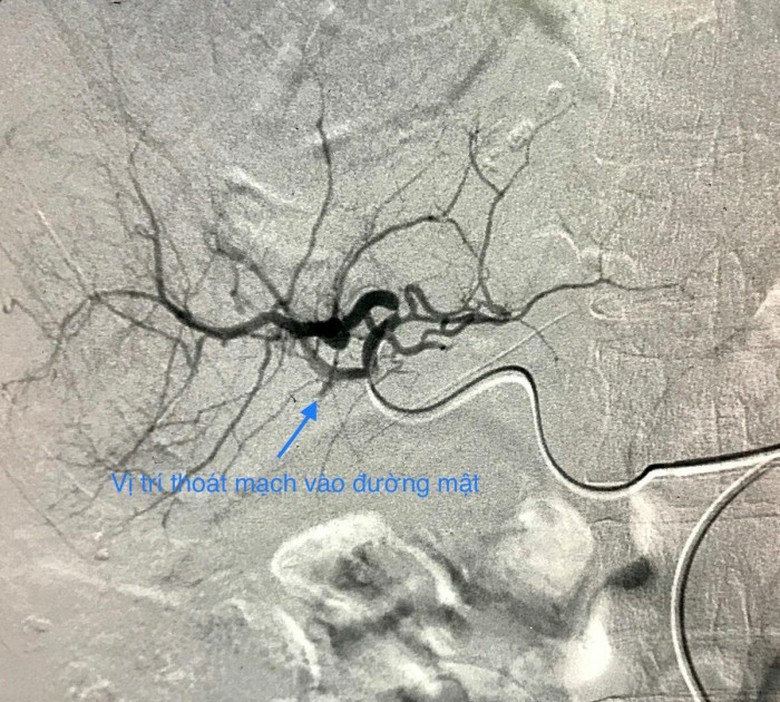

Hình ảnh trước khi bệnh nhân được can thiệp

Biểu hiện lâm sàng là choáng mất máu do chảy máu ồ ạt vào đường mật hoặc khoang phúc mạc. Bệnh nhân có thể đại tiện phân đen do máu chảy vào đường mật hoặc bụng căng chướng do máu chảy vào khoang phúc mạc.